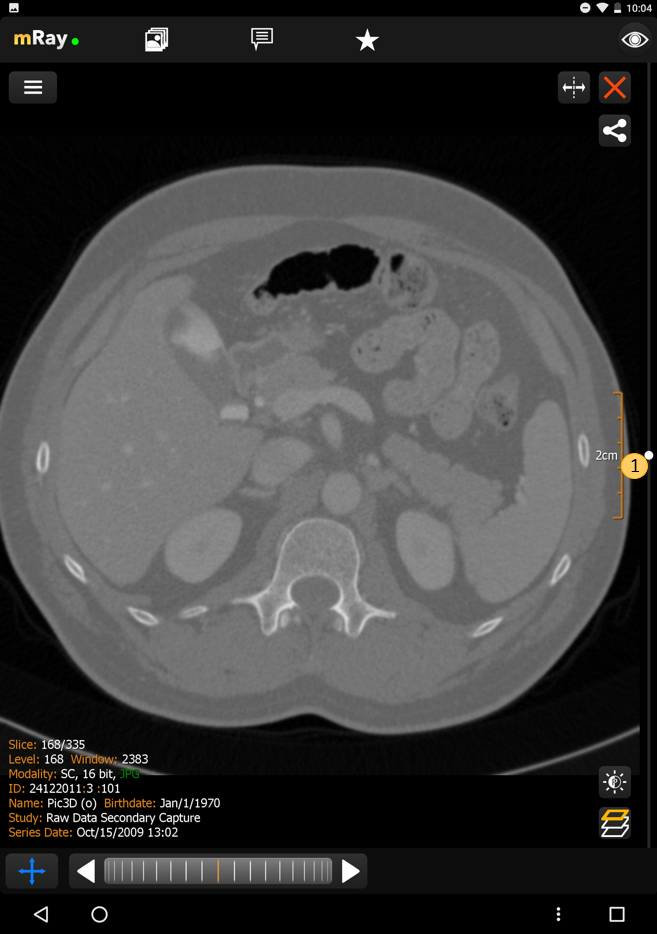

The MPR views allow you to open up multiple views at once ([abbr-mpr] View). Following screenshot shows the MPR view:

The Screenshot shows the original view of a dataset, the locally computed reconstructions (MPRs) and information to the viewed dataset.

-

Add more views here

.

The maximum number of views is 2 on smartphones and 4 on tablets.

Temporarily display view in a fullscreen state and back to previous state using maximize

.

The maximum number of views is 2 on smartphones and 4 on tablets.

Temporarily display view in a fullscreen state and back to previous state using maximize  and minimize

and minimize  icons.

icons. -

Indication of the current view direction in relation to the original image stack. You can change the view direction by pushing this button

.

. -

Use this button

to synchronize with the active view.

See Synchronized Views for more details.

to synchronize with the active view.

See Synchronized Views for more details. -

Shows the reference lines depending on the other opened views. These can be configured in the Toolmenu

You can change the perspective with the MPR perspective button (Point 2). This allows you to switch between axial, sagittal and coronal. The button in the top right corner (Point 1), allows you to open or close a view. If there is more than one view, a button to synchronize view adjustments will appear (see Synchronized Views). In order to interact with a view you have to select the appropriate view first. Therefore tap on the view. The selected view will be highlighted.